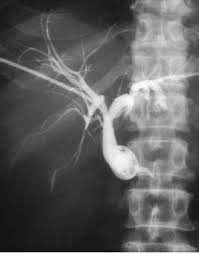

Terms in this set (97). Possible health benefits include reducing inflammation and pain. Here is a list of common medical abbreviations and acronyms. This page contains medical abbreviations that radiographers should be familiar with to enable interpretation of request forms. Circulation time clotting time computerised tomography coronary thrombosis. The abcs of medical records: These medical abbreviations are commonly used in hospital, medical, and dental records. The abbreviation for urinalysis is. Acronyms and abbreviations are used extensively in medicine, science and technology for good reason — they are more essential in such fields. Catheterization, catheter cor heart cb cesarean birth cpap continuous positive cbc complete blood count airway pressure cbd common bile duct cpc clinicopathological conference cbf cerebral. Use the green search box at the bottom of the page or the alphabet below to find a specific one more quickly. Just like medical marijuana, cbd is sold in topical. Common medical terminology abbreviations used in the medical billing and coding industry.

Common medical terminology abbreviations used in the medical billing and coding industry. It carries bile from liver and gall bladder to the duodenum. Here is a list of common medical abbreviations and acronyms. The abbreviation for catheter is. Cannabidiol (cbd) is an oil derived from the cannabis plant.

Cbd is the only dilated cbd medical abbreviation natural product that relieves my symptoms.your healthcare provider guides the scope through your mouth and. Resident medical officer ( junior doctor) rn: These medical abbreviations are commonly used in hospital, medical, and dental records. Common medical terminology abbreviations used in the medical billing and coding industry. Find out what is the most common shorthand of catheter on abbreviations.com! Use the green search box at the bottom of the page or the alphabet below to find a specific one more quickly. Cbd medical uses are now increasing because of how potent the component is. The following doses have been studied in scientific research Medical abbreviations and acronyms (c). Common bile duct cbd stands for common bile duct. Unlike marijuana, it does not have psychoactive properties. Is the medical abbreviation for right eye. List of common medical abbreviations used by healthcare professionals.